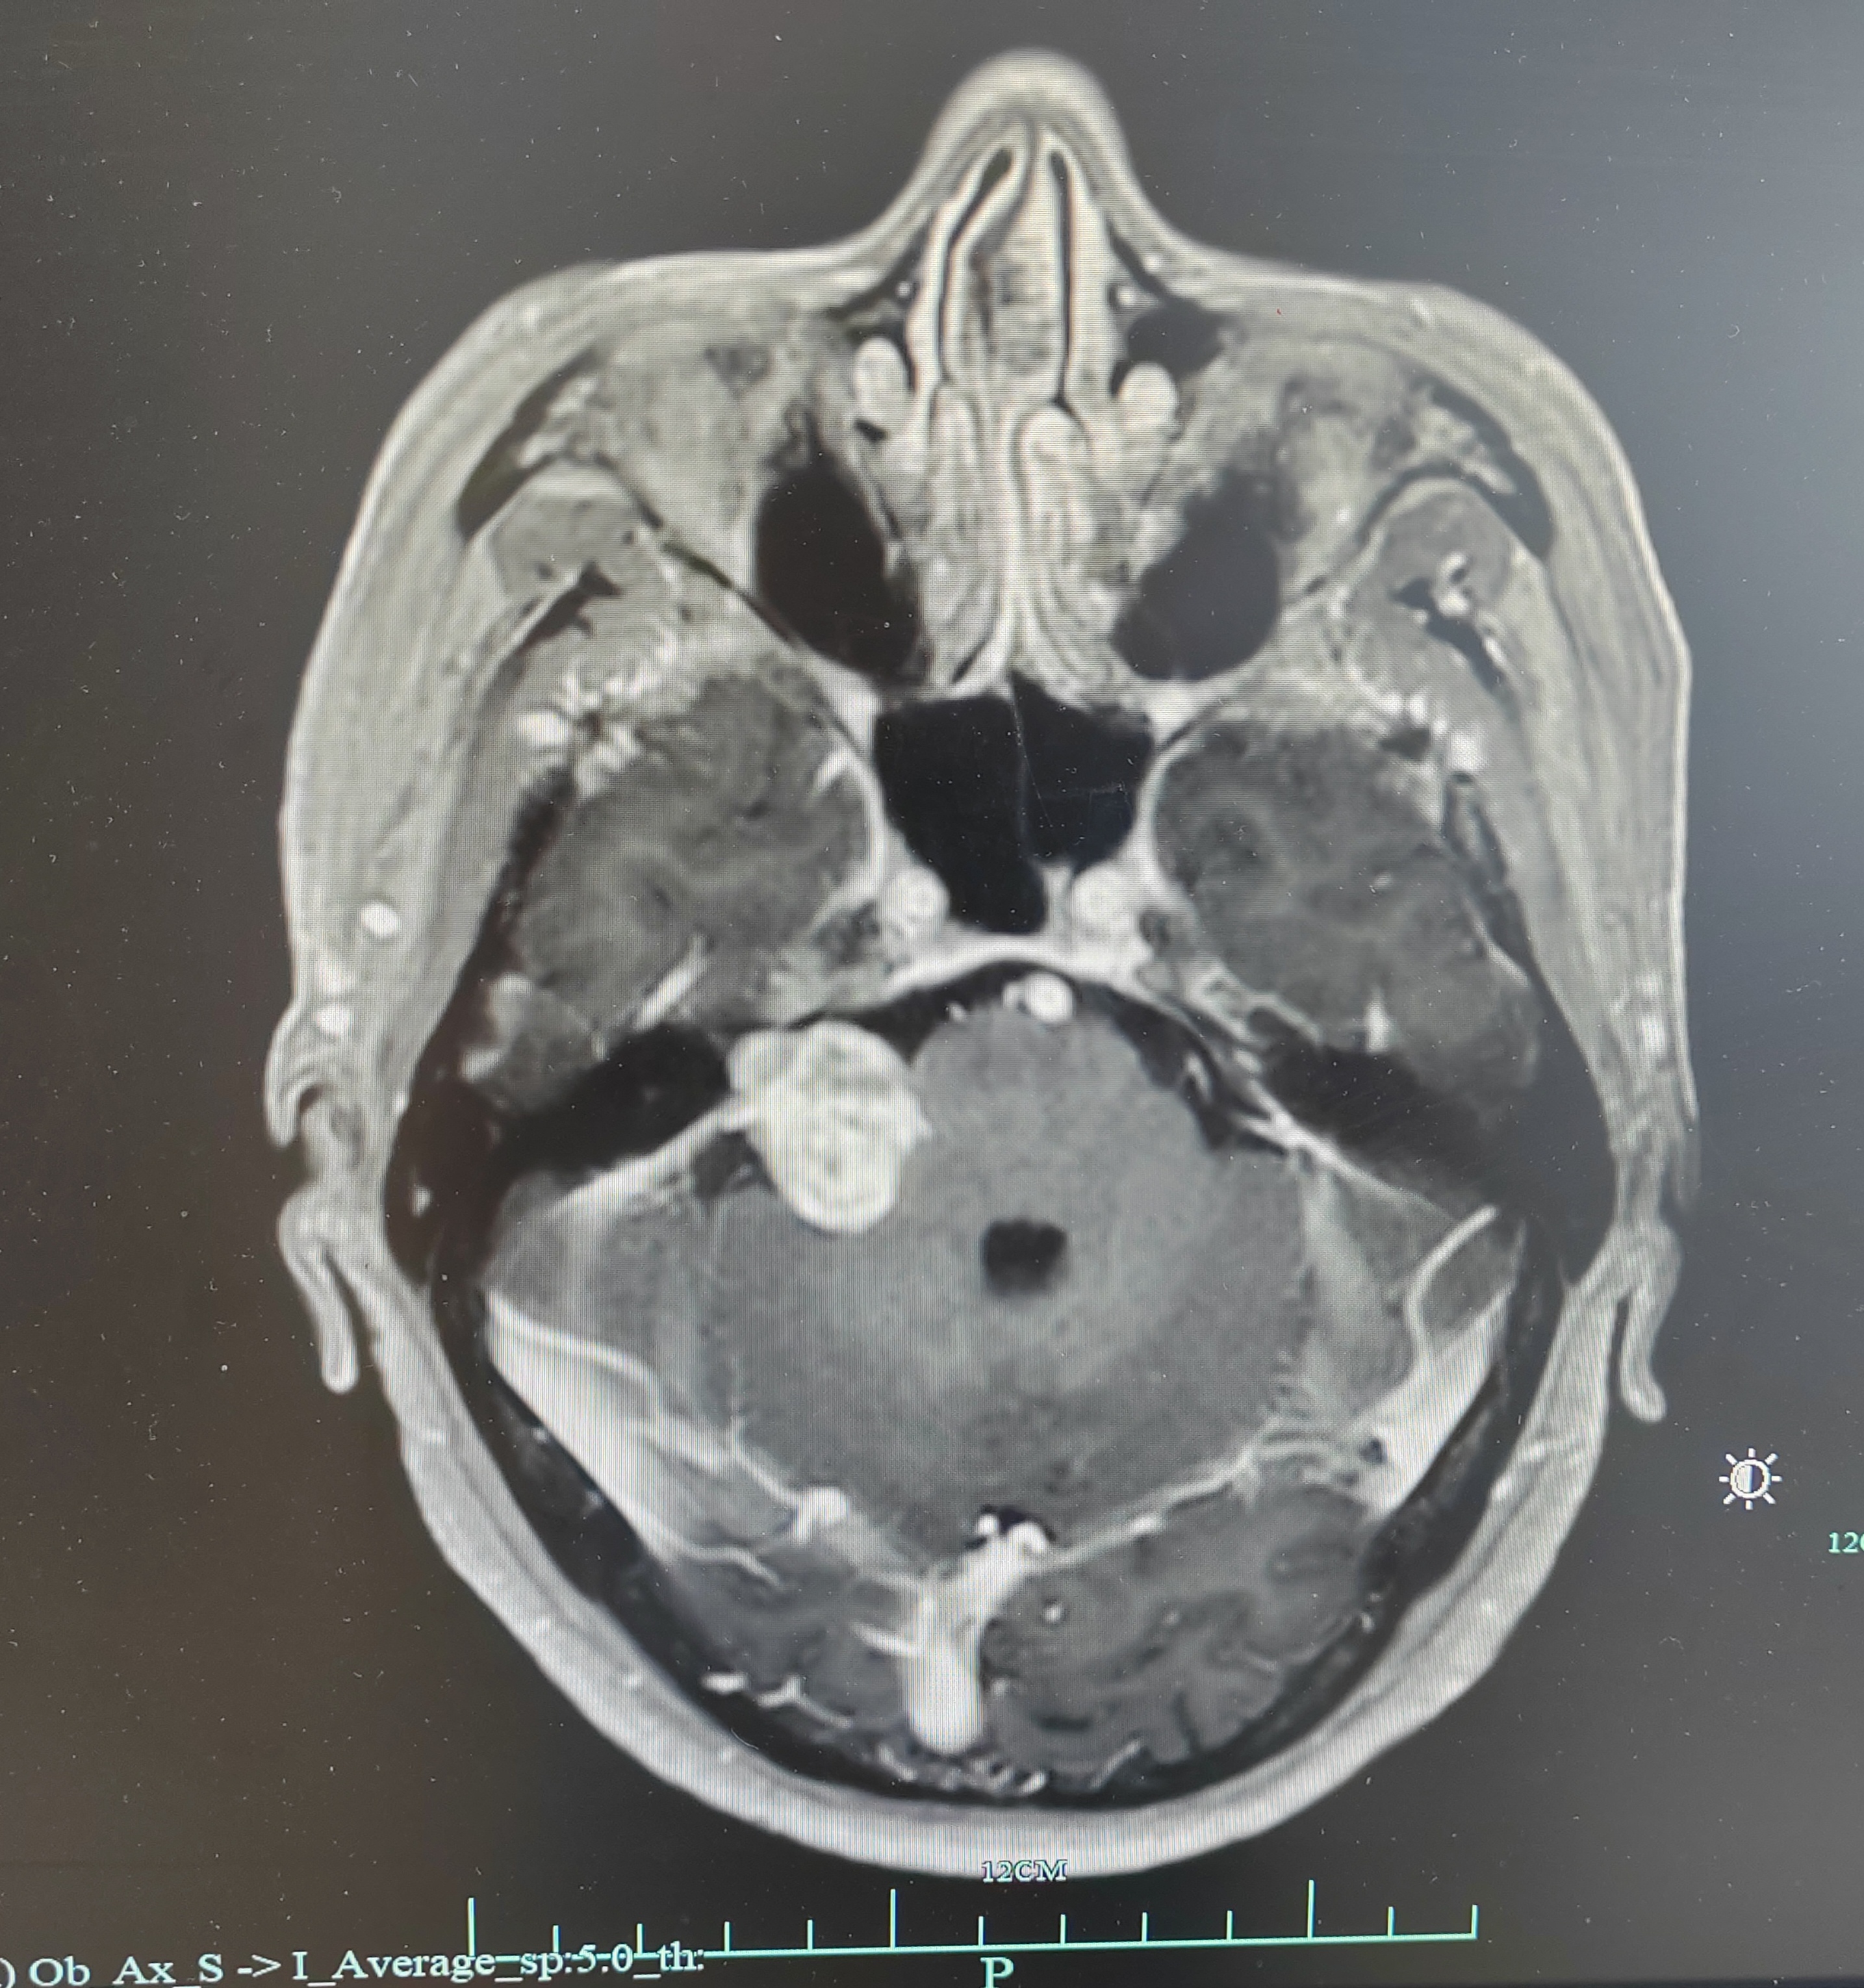

右侧桥小脑角3厘米占位,内听道扩大,肿瘤血供丰富,上方达天幕,与脑干关系密切,蛛网膜间隙不明显,颈静脉球相对高位,诊断考虑:右侧前庭神经鞘瘤(听神经瘤)